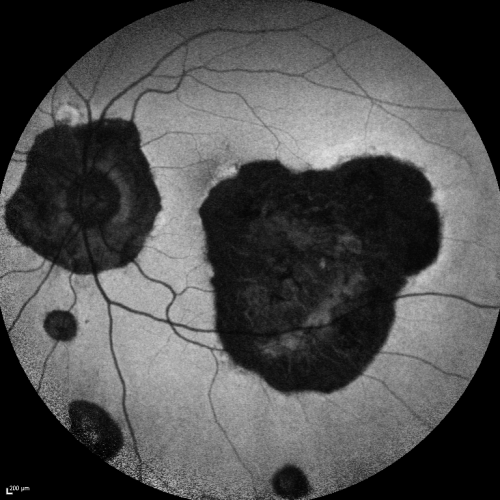

Ocular Histoplasmosis both Eyes - Laser Right Eye Only Fundus Autofluoresence

58-year-old woman who lost vision as a child in the left eye from ocular histoplasmosis.  She used to play in her attic and she was told by her pulmonary doctor that is probably where she picked it up.  She had laser in the right eye for a leaky lesion back in 1990.  OD 20/25,  OS 20/200.